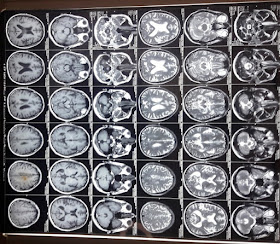

Radiological investigation images: